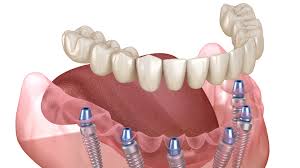

Dental Implants are surgical grade root devices that support permanent tooth prosthetics. A crown is mounted atop the implant for a long –lasting and natural looking smile, also implants help prevent bone atrophy in the jaw.

The placement of dental implants is a multi –step process that typically takes between 6 to 9 months to complete. It begins with a surgical procedure and titanium implant placed at where natural tooth root once was.

The gums are sutured shut over the implant and wait for several months while it heals and begins fusing with the surrounding bone.

After completion of the healing period, you ‘ll return to be fitted for permanent crowns.